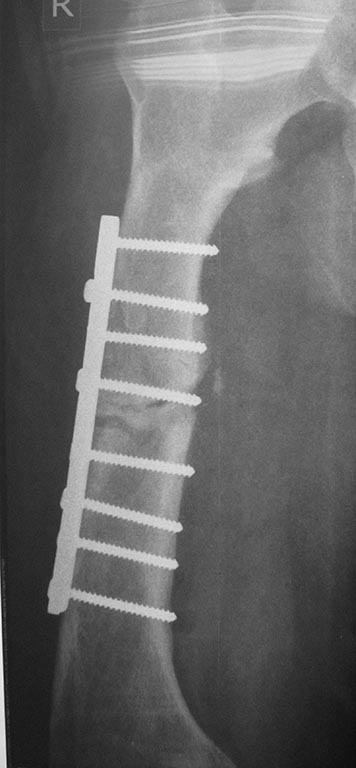

[Ortho] перелом бедра с исходной деформацией

Выкладываю, как и обещал. За репозицию педплечья не осуждайте!